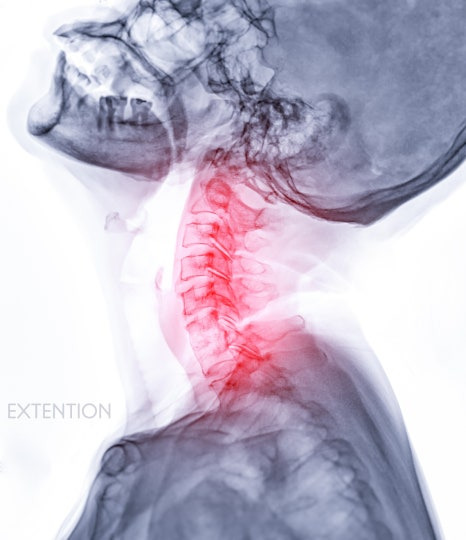

목디스크, 팔 저림으로 이어지는 이유

목디스크는 목만 불편한 게 아니라 팔과 손까지 영향을 주는 경우가 많습니다. 그 이유는 경추에서 나온 신경이 어깨와 팔, 손까지 이어져 있기 때문이에요. 디스크가 튀어나오면서 이 신경을 누르면, 실제 문제 부위와 다른 위치에서 증상이 나타나게 됩니다.

|

목 주변 긴장감

어깨 쪽 당김

팔 저림 또는 감각 둔화